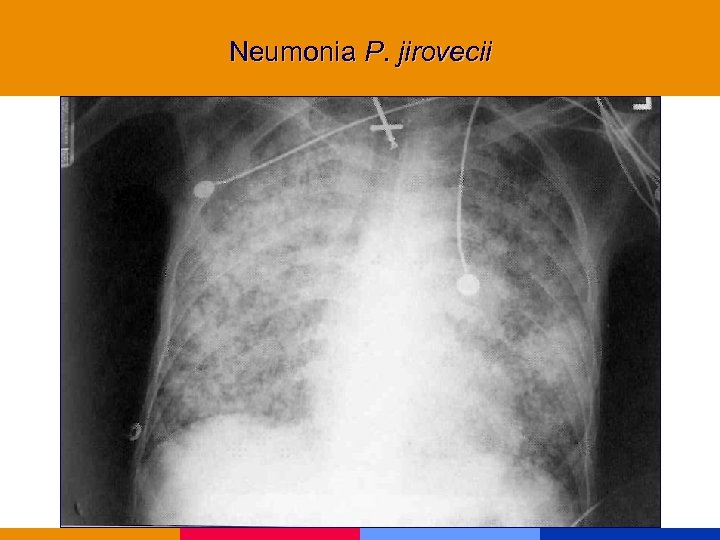

Neumonía por Pneumocistis jirovecii

Neumonía por Pneumocistis jirovecii

Neumonía por Pneumocistis jirovecii § CD 4 < 200 mm 3 § Comienzo insidioso: fiebre, tos seca, disnea. Hallazgos al examen físico incaracterísticos. § Lab: VSG: 50 mm. LDH, valor diagnóstico y pronóstico. Hipoxemia. § Rx infiltrado intersticial difuso, neumatocele, neumotórax. § TC de alta resolución.

Neumonía por Pneumocistis jirovecii § CD 4 < 200 mm 3 § Comienzo insidioso: fiebre, tos seca, disnea. Hallazgos al examen físico incaracterísticos. § Lab: VSG: 50 mm. LDH, valor diagnóstico y pronóstico. Hipoxemia. § Rx infiltrado intersticial difuso, neumatocele, neumotórax. § TC de alta resolución.

Neumonia P. jirovecii

Neumonia P. jirovecii

Neumonia P. jirovecii

Neumonia P. jirovecii

Neumonia P. jirovecii

Neumonia P. jirovecii

Neumonia P. jirovecii

Neumonia P. jirovecii

Neumonia P. jirovecii

Neumonia P. jirovecii

Neumonia P. jirovecii

Neumonia P. jirovecii

Neumonia P. jirovecii

Neumonia P. jirovecii